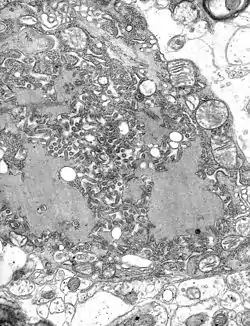

TEM micrograph with numerous rabies virions (small, dark grey, rodlike particles) and Negri bodies (the larger pathognomonic cellular inclusions of rabies infection)

The rabies virus is the type species of the Lyssavirus genus, in the family Rhabdoviridae, order Mononegavirales. Lyssavirions have helical symmetry, with a length of about 180 nm and a cross-section of about 75 nm.[33] These virions are enveloped and have a single-stranded RNA genome with negative sense. The genetic information is packed as a ribonucleoprotein complex in which RNA is tightly bound by the viral nucleoprotein. The RNA genome of the virus encodes five genes whose order is highly conserved: nucleoprotein (N), phosphoprotein (P), matrix protein (M), glycoprotein (G), and the viral RNA polymerase (L).[34]